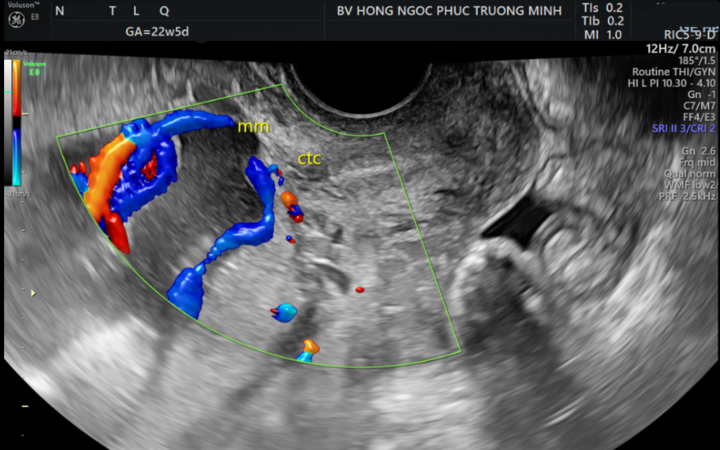

hát hiện mắc đồng thời dây rốn bám màng và mạch máu tiền đạo, chị N.T.L.Q (27 tuổi, Hà Nội) được các bác sĩ Sản khoa tại BVĐK Hồng Ngọc quản lý thai kỳ sát sao và hỗ trợ kịp thời. Nhờ sự can thiệp chủ động và chính xác của các bác sĩ, chị Q đã vượt cạn thành công, đón con chào đời an toàn.